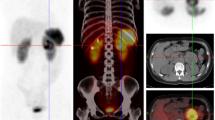

Following this result, we transferred CA9 immunostaining to routine clinical practice in our pathology department and studied its expression prospectively in 107 consecutive paragangliomas, in parallel to the paraganglioma genetic testing performed by the next-generation sequencing assay. We considered as “negative”, the tumors presenting no CA9 expression or a cytosolic labeling (Fig. 1a) and ‘positive’, the tumors in which we identified CA9 membrane staining, in either one or a few cells (Fig. 1b) or all tumor cells on a section (Fig. 1b). It is worth noting that sustentacular labeling was observed, and was not considered as a tumor cell positive staining (Fig. 1d).

CA9 protein expression in the prospective study. In non-VHL-mutated paraganglioma, CA9 protein expression is observed in the cytosol of tumor cells (a), while membrane staining of tumor cells (black arrows) was only found in VHL-mutated paraganglioma (b–d). Sustentacular staining should not be considered as a tumor membrane labeling (red arrows in D). The different samples were classified in four groups depending on the distribution of CA9 staining from 0.1% to almost 100% of tumor cells. The proportion of tumors classified in each group is shown in e

We observed the presence of membrane CA9 labeling in 25 tumors. Among them, 5% presented CA9 membrane staining in only 1 or 2 isolated cells on the whole tissue section, while 35% of cases exhibited between 10 and 20 isolated positive cells (representing <1% of all cells on the slide). Focal areas of positive cells representing 1–20% of the tissue section were seen in 35% of cases. Finally, 25% of samples showed a widespread positive membrane staining, on 80–100% of the tumor cells (Fig. 1e). Next-generation sequencing identified a VHL variant in 18 of them (9 at germline level, 1 mosaic, and 8 at somatic level) (including one occurring in a germline SDHA-mutated paraganglioma) (Table 1). Among them, there were 16 different variants including 11 missense, one deletion, one splice site, one frameshift, one synonymous, and one substitution affecting the translation termination codon. Eleven of them were classified as pathogenic or likely pathogenic in the UMD-VHL database (http://www.umd.be/VHL/) and/or the ClinVar database (https://www.ncbi.nlm.nih.gov/clinvar/?term = VHL%5Bgene%5D) (Supplementary Table 1b). The germline missense variant p.(Gly144Arg) was identified in a 29-year-old patient presenting a perirenal paraganglioma. It was previously reported in a patient with malignant pheochromocytoma [25] and was also associated with polycythemia [26]. The p.(Pro138Pro) variant was identified in a patient with a family history of VHL disease and was functionally validated by mRNA analysis, which showed a splicing alteration (data not shown). This variant was already published with evidences for pathogenicity [27]. Three of the 16 VHL variants were not previously reported. The c.640T>G germline variant, leading to a protein extension with the addition of a tail of 13 new amino acids, was found in a patient affected with a single pheochromocytoma at 67 years old. The missense germline variant p.(Ala122Val) was found in a patient with bilateral pheochromocytoma diagnosed at 47 years old. The p.Val87Glu somatic variant was identified with an allelic ratio of 8% in a pheochromocytoma developed by a 29-year-old patient.